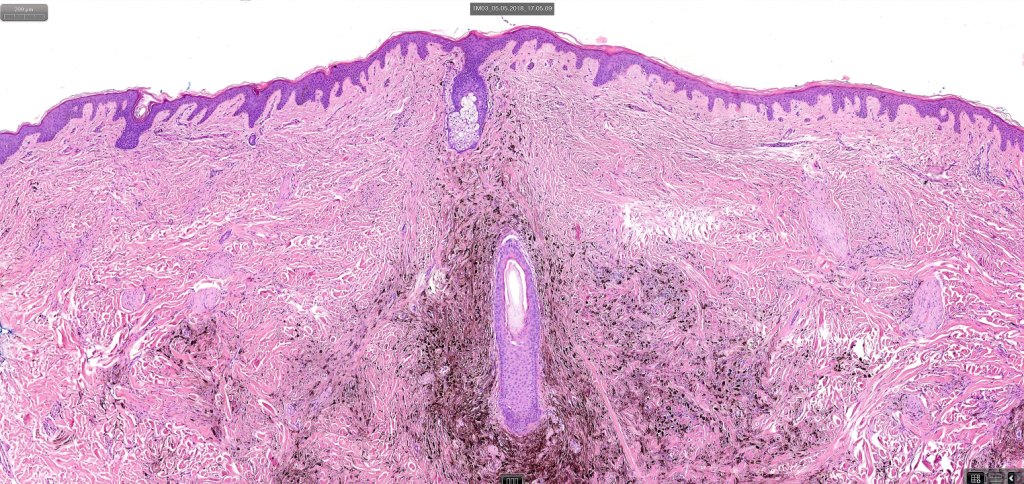

Neurocristic hamartoma

This is exceedinly rare and represents a hamartomatous lesion of neural crest origin The scalp is most often affected but although it can also present on the face, neck, buttock and elsewhere. It presents as folliculocentric brown or blue/black papules and nodules sometimes associated with alopecia. Exceptionally melanoma supervenes.

Histologically it presents in varying proprtions of banal and blue nevus accompanied by scattered dendritic cells associated with neurofibroma-like spindle cells and Schwann cell nodules with Meissner corpusces surrounded by sustentacular EMA positive cells. The lesion typically ensheathes the hair follicles.